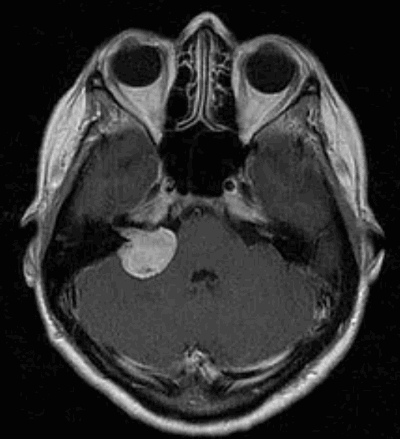

Вестибулярная шваннома (невринома VIII нерва, акустическая невринома) представляет собой доброкачественное новообразование, возникающее из шванновских клеток вестибулярной порции VIII нерва.

Заболеваемость невриномами слухового нерва составляет примерно 1 случай на 100000 населения в год. Каждый год в Российской Федерации появляется 1500 новых случаев неврином слухового нерва. Среди первичных интракраниальных опухолей вестибулярные шванномы вестибулярные шванномы занимают 4-е место (после глиом, менингиом и аденом гипофиза), составляя до 6-10% всех верифицированных опухолей мозга и поражая преимущественно лиц работоспособного возраста (30-60 лет), на который приходится более 80% случаев. Вестибулярные шванномы составляют около 30% опухолей задней черепной ямки и до 90% новообразований мосто-мозжечкового угла. Несколько чаще встречаются у женщин, чем у мужчин, примерное соотношение 3:2.

Диагностика

Наиболее информативным методом выявления вестибулярных шванном является МРТ головного мозга с контрастным усилением в режиме Т1 и Т2. Это исследование позволяет определить размеры опухоли, наличие перитуморозного отека, наличие признаков окклюзионной гидроцефалии, которая может быть следствием сдавления опухолью IV желудочка. Кроме этого МРТ позволяет провести дифференциальную диагностику с другими опухолями схожей локализации (чаще с менингиомой задней грани пирамиды височной кости). Еще одним стандартом диагностики является КТ в костном режиме. Независимо от снижения слуха стандартом является проведение аппаратной аудиографии.